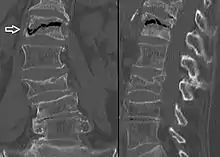

| Example of vertebral compression fracture. | |

A compression fracture is a collapse of a vertebra. It may be due to trauma or due to a weakening of the vertebra (compare with burst fracture). This weakening is seen in patients with osteoporosis or osteogenesis imperfecta, lytic lesions from metastatic or primary tumors,[1] or infection.[2] In healthy patients, it is most often seen in individuals suffering extreme vertical shocks, such as ejecting from an ejection seat. Seen in lateral views in plain x-ray films, compression fractures of the spine characteristically appear as wedge deformities, with greater loss of height anteriorly than posteriorly and intact pedicles in the anteroposterior view.[3]

Compression fractures are usually diagnosed on spinal radiographs, where a wedge-shaped vertebra may be visible or there may be loss of height of the vertebra. In addition, bone density measurement may be performed to evaluate for osteoporosis. When a tumor is suspected as the underlying cause, or the fracture was caused by severe trauma, CT or MRI scans may be performed.